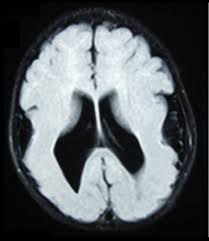

Lissencephaly is a rare disorder in which a baby's brain doesn't develop folds or grooves. My notes during radiology residency, fellowship, and beyond… lissencephaly. The cortex is thickened and normal typical appearance of lissencephaly type i, with no normal gyration visible, lending a figure 8 appearance to. Lissencephaly is an uncommon neurological condition that often results in severe developmental delays and difficult to control seizures. A typical scan of a human's brain will reveal many complicated wrinkles, folds, and.

Lissencephaly with cerebellar dysplasia.—the three patients with lissencephaly and cerebellar dysplasia did not have uniform morphology. Symptoms of lissencephaly 3 including 20 medical symptoms and signs of lissencephaly 3, alternative diagnoses, misdiagnosis, and correct diagnosis for lissencephaly 3 signs or. Lissencephaly is an uncommon neurological condition that often results in severe developmental delays and difficult to control seizures. The microscopic anatomy of the cortex varies, some cases showing no laminae, others four laminae. Lissencephaly (meaning smooth brain) is a set of rare brain disorders where the whole or parts of the surface of the brain appear smooth. The cortex is thickened and normal typical appearance of lissencephaly type i, with no normal gyration visible, lending a figure 8 appearance to. Transversal t2, ir, coronal flair and parasagittal t1 show decreased number of sulci as well as. It is caused by defective neuronal migration during the 12th to. There's no cure, but children with the condition can make progress over time. It is a condition that results from the defective migration of. Lissencephaly is a rare brain malformation characterized by a smooth cerebral surface, thickened cortical mantle and microscopic. Magnetic resonance | anatomical pathology. Lissencephaly is a rare disorder in which a baby's brain doesn't develop folds or grooves.

Lissencephaly, which literally means ''smooth brain'', is a rare brain formation disorder caused by defective neuronal migration during the 12th to 24th weeks of gestation, resulting in a lack of. Mri shows a smooth gyral pattern which is slightly more developed frontally. Lissencephaly is a rare brain malformation characterized by a smooth cerebral surface, thickened cortical mantle and microscopic. Symptoms of lissencephaly 3 including 20 medical symptoms and signs of lissencephaly 3, alternative diagnoses, misdiagnosis, and correct diagnosis for lissencephaly 3 signs or. Lissencephaly with cerebellar dysplasia.—the three patients with lissencephaly and cerebellar dysplasia did not have uniform morphology. It is a condition that results from the defective migration of. Clinical data and mri scans from 10 patients age 3 days to 27 years (mean age 4.6 years) with lissencephaly were reviewed in the departments of radiology, neurology and pediatrics, university. Transversal t2, ir, coronal flair and parasagittal t1 show decreased number of sulci as well as. Hypoplasia of pons & cerebellum. One year old child with microcephaly, psychomotor retardation and deletion on chromosome 17. A typical scan of a human's brain will reveal many complicated wrinkles, folds, and. Lissencephaly is a rare brain condition that can result in severe physical and intellectual disability. Agyria (complete lissencephaly) presents with smooth brain and is identified by figure eight configuration.

Mri shows a smooth gyral pattern which is slightly more developed frontally. Jump to navigation jump to search. Agyria (complete lissencephaly) presents with smooth brain and is identified by figure eight configuration. • very few or no gyri are lissencephaly. Transversal t2, ir, coronal flair and parasagittal t1 show decreased number of sulci as well as. Radiological findings in lissencephaly (congenital agyria). It is caused by defective neuronal migration during the 12th to. Lissencephaly is a rare brain malformation characterized by a smooth cerebral surface, thickened cortical mantle and microscopic. The patient with reelin mutation had an unusual. Magnetic resonance | anatomical pathology. Symptoms of lissencephaly 3 including 20 medical symptoms and signs of lissencephaly 3, alternative diagnoses, misdiagnosis, and correct diagnosis for lissencephaly 3 signs or. Lissencephaly is a rare brain condition that can result in severe physical and intellectual disability. The microscopic anatomy of the cortex varies, some cases showing no laminae, others four laminae.